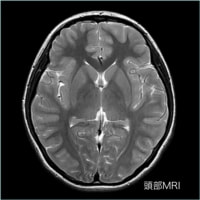

MRI装置

MRIとは?

MRIとは核磁気共鳴画像法(英語: Magnetic Resonance Imaging)の略です。

核磁気共鳴(nuclear magnetic resonance, NMR)現象を利用して生体内の内部の情報を画像にする方法です。

診断において断層画像という点ではレントゲンCTと一見よく似た画像が得られることが出来ます。

しかし、MRIは強力な磁石を使うことより放射線被曝はありません。

また、放射線CTと原理が異なるため、それぞれの特徴を吟味しCTと組み合わせて画像診断を行うことがあります。

1980年代初頭に臨床の場に登場したMRIは大いなる発展を遂げ、そして今でも進化し続けています。

軟部組織のコントラストに優れ、様々なコントラストパラメーターを有するMRIは、頭頚部、体幹部、脊椎・脊髄、整形領域、心臓領域とほぼ全身に渡る断層画像をあらゆる角度で撮像できます。

当院導入のGE社は超伝導MRIの稼動実績において、日本だけでなく世界においてもトップシェアを維持し続けて、良質な画像を得ることが出来ます。

当院のMRIの特徴

今回当院では画像描出に定評のあるGE社の1.5TのMRIを採用しました。

この装置は光デジタル伝送技術を採用し、外部ノイズの混入を抑え、劣化のない高画質な画像を得ることができます。

これらのことより、

- 撮影時間の短縮

- 良好な画像を得る

という難しい難題をクリアしたため、当院で採用となっています。

放射線部スタッフ一同ともより高画質の提供を出来るように努力してまいります。